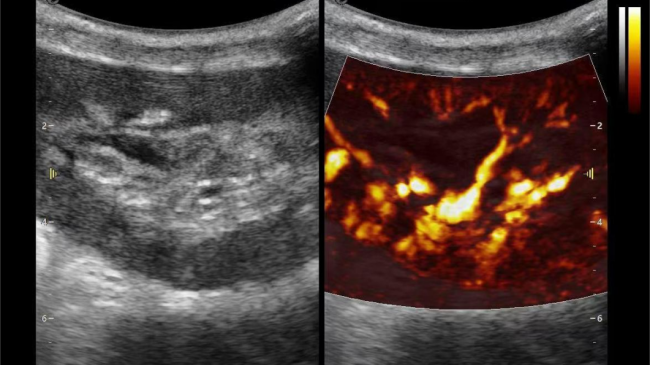

术中:导航仪,实时监测为手术保驾护航

1) 实时查看血管吻合情况,确保新肾"通电"后动、静脉血流是否畅通;

2) 监测肾门处血流频谱及时干预血栓的形成,减少术后血管并发症的发生率;

3) 观察肾皮质的血流灌注情况,评估肾移植的成功率。

术后:监护仪,做好新肾的"健康管家"

1) 术后24小时全天监测新肾大小和血流,预警血栓,积水等并发症;

超微视血流显像显示肾脏五级血管

微米级超高分辨率血流信号显像

肾脏的灌注评估,RI/VI量化数据

超微视血流显像评估肾移植术后灌注情况